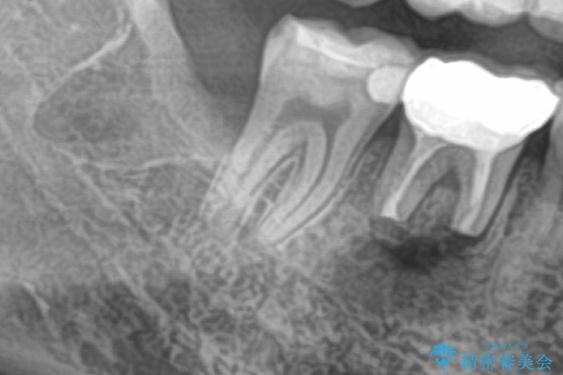

- 右下の親知らずを抜きたいとのことで来院された患者様です。

CTで神経の位置などを確認し、抜歯術を行いました。

一週間後に抜糸を行いました。